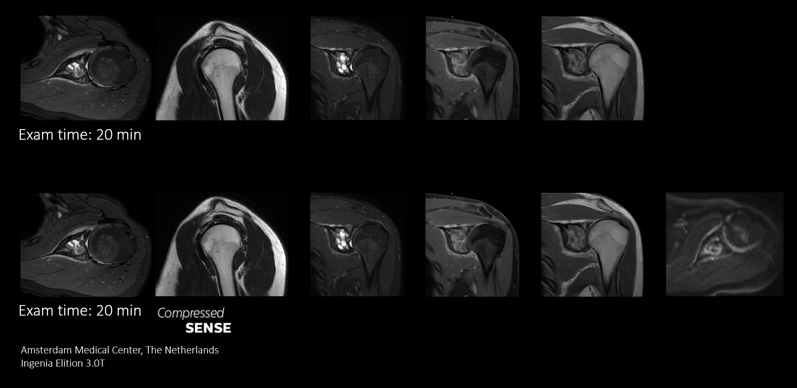

Enables up to 64% improvement in spatial resolution, within the same scan time1

Compare the image quality of an MRI scan performed with Compressed SENSE MRI software versus a conventional scanning technique

voxel size: 0.4 x 0.6 x 2.5mm voxel size: 0.3 x 0.3 x 2.5mm

The key to the Philips Compressed SENSE implementation is that it is universally applicable to all 2D & 3D scans as well as all body parts – that makes an enormous difference.”

Dr. Lawrence N Tanenbaum, RadNet, Beverly Hills, CA, USA